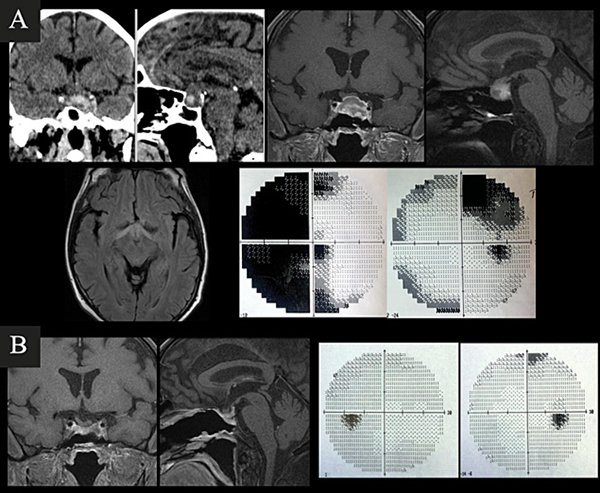

Caso 1. A. Preoperatorio. Varón de 63 años, hipertenso y antiagregado con AAS que consultó por cefalea, náuseas, vómitos y síncope. Al examen físico presentaba disminución de la AV en ojo izquierdo + ptosis palpebral y midriasis izquierdas. En la TC y RM de cerebro e hipófisis se evidenciaba una lesión selar con componente hemorrágico y edema de la vía óptica. El CVC evidenciaba hemianopsia temporal izquierda y cuadrantopsia superior derecha. B. Postoperatorio. RM que demuestra resección completa y CVC normal.

Caso 2. A. Preoperatorio. Varón de 54 años que consultó por cefalea, náuseas y vómitos. Al examen físico presentaba disminución de la AV y III par completo izquierdo +. En la TC y RM de cerebro e hipófisis se evidenciaba una lesión selar-supraselar voluminosa con contenido hemático. B. Postoperatorio. RM que demuestra resección completa de la lesión.